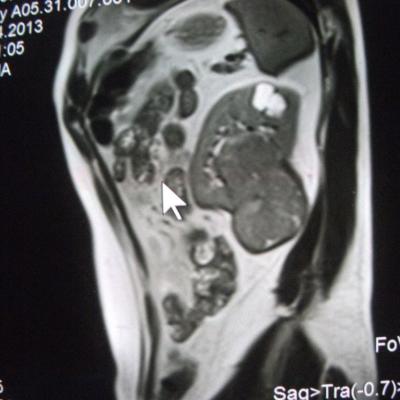

такое заключение: Левая почка: расположена обычно, увеличена, общими размерами около 13х5,5см. В области средней и нижней трети почки определяется объёмное образование неправильной формы, деформирующее наружный контур почки, распространяющиеся с чашечно-лоханочную систему. Опухоль имеет четкие неровные бугристые контуры с наличием псевдокапсулы, неоднородной структуры с признаками распада, максимальными размерами около 78,7х47х48мм